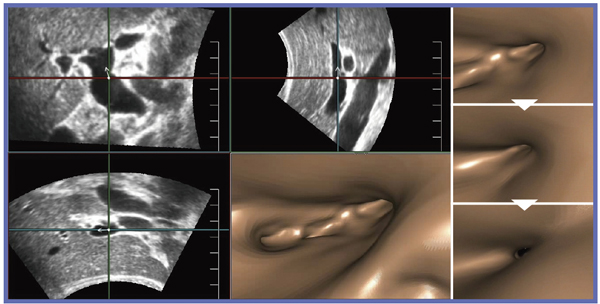

胆管の拡張のみで,腫瘍や結石は認められず,5〜7年経過観察を行っている症例である。図1aは,Cavity(USCP)による画像で,肝門部〜肝外胆管部分の再構成画像である。胆管は意外と薄く,主として左肝管に拡張があることがわかる。Bモード画像でも,胆管の拡張の状況は把握できる。しかし,Cavity(USCP)では全体像の把握が容易である。

同部位のFly Thruによる画像では,下部胆管から肝門部方向に移動しながら肝管合流部を観察することができる。胆管内では,腫瘍や結石を認めず,拡張のみであることがわかる。さらに,合流部では左肝管と,前区域枝,後区域枝に向かう分岐を確認できる(図1b)。Fly Thruでは,それぞれの分枝を選択して,左肝管,前区域枝,後区域枝と視点を移動して内腔を観察することができ,通常は胆管鏡でなければ得られない情報を簡単に描出できる。Fly Thruで,肝門部から左肝管の中に入ると,上流側までスムーズに追うことができた(図2)。

図1 症例1:胆管拡張,肝管合流部のCavity(USCP)(a)とFly Thru(b)

図2 症例1:左右肝管合流部から左肝管に向かうFly Thru画像